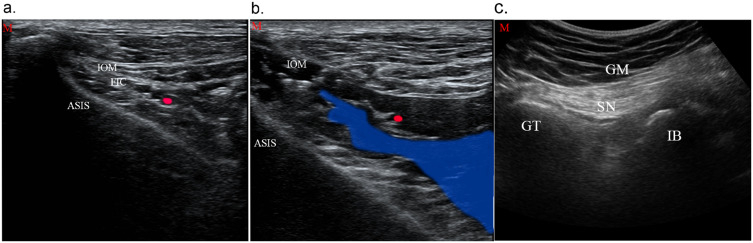

Abstract Image